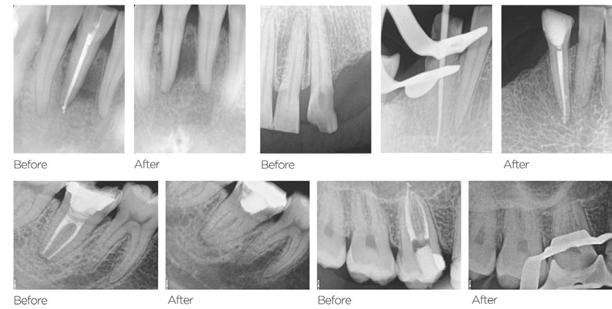

Figures 1A-1C: 1A. Preoperative X-ray. 1B. Immediate postoperative X-ray. 1C. Follow-up after 9 years and 10 months

Periapical radiographs and medical records corresponding to 48 teeth with IRR were collected from five different dental offices. The following aspects of the IRR were then analyzed: number of tooth in which it was found, location, presence or absence of periapical radiolucency, shape of the affected dentin walls, type of treatment performed, filling technique used, degree of adaptation of the filling to the resorption, presence of perforation communicating with the periodontium. Of the 48 cases diagnosed with IRR, all have been endodontically treated, and 29 of them have received initial treatments and 19 retreatments. Of the total number of cases, 29 had long-term follow-ups, while 19 do not have them.

Of the total, 29 had long-term radiographic follow-ups that ranged from a minimum of 6 months to a maximum of 25 years, with an average of 5 years, 4 months. Of the cases with radiographic follow-ups, 28 were considered successful and one failure (Table 2). Of the successful cases, 17 corresponded to treatments and 11 to retreatments (Figures 1A, 1B, 1C, and 2A, 2B, 2C). The tooth considered failed was a retreatment.

The radiographic appearances that generates the IRR are varied. The most common one observed in the present study was a circular shape with regular and symmetrical walls specially in single-rooted teeth (Figure 4A), although there were also some

Figures 2A-2C: 2A. Preoperative X-ray. 2B. Immediate postoperative X-ray. 2C. Follow-up after 18 years and 6 months

Figures 3A-3C: 3A. Preoperative X-ray. 3B. Immediate postoperative X-ray. 3C. Follow-up after 4 years

irregular ones with asymmetrical walls (Figure 4B). In molars, when resorption affects the pulp chamber, it was commonly seen as an irregularly shaped radiolucent cavity2 (Figure 4C).

Figure 4A-4C: 4A. Maxillary lateral incisor with an internal resorption at the coronal third. 4B. Mandibular canine with an internal resorption in the middle-apical area. 4C. Mandibular molar with an irregular internal resorption in the coronal portion Figures 5A-5C:

5A. Preoperative X-ray. 5B. Immediate postoperative X-ray. 5C. Follow-up after 1 year and 9 months EP